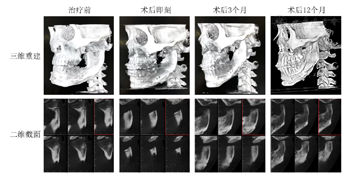

5.密切关注左侧关节复位情况,在正畸治疗的引导下左侧关节逐渐恢复髁突形态,并复位至关节窝内,在术后12个月时改建形成类髁突样形态(图12)。术后12个月时进行下颌运动轨迹记录,开口型轻度左偏,开口度正常,双侧颞肌肌力基本一致,左侧咬肌肌力较右侧弱(图13)。

3.正颌外科完成左侧髁突切除及双颌手术:Le fort Ⅰ型截骨后摆正上颌平面(图9A),经导航完成左侧髁突切除(图9B),术中可见翼外肌纤维占据关节窝,髁突难以按照数字设计复位至关节窝内(图9C)。术后即刻CBCT显示咬合平面摆正,左侧髁突切除后升支骨段未能实现数字化设计的复位(图10)。

术后正畸:术后1个月开始进行正畸加力,0.014-0.019×0.025镍钛丝进行排齐整平,排齐早期开始34、45与上颌种植钉进行局部垂直牵引,尽早纠正左侧前磨牙区开

的同时起到稳定颌位的作用(图11)。

,因此设计在术中于24、25之间植入种植支抗,并在术后早期配合34、35与上颌种植支抗的垂直牵引,有效伸长34、35的同时避免牙-牙牵引可能引起的上颌前磨牙伸长,从而降低咬合平面复发的风险,建立前磨牙区的尖窝交错的咬合关系,从而稳定左侧颌骨位置。同时,术后正畸这一方向的牵引,可以促进升支骨段向上移位,在牵引的诱导下回到关节窝内,逐渐形成新的髁突形态,恢复关节功能。

通过本病例的治疗,我们认为在正颌术中髁突切除后利用升支骨段直接建立"假关节"的方案是难以实现的,但对于此类患者的术后下颌功能仍可以抱有积极的态度。成人患者在髁突切除后升支部分的骨改建在术后3个月内十分活跃,残余髁颈在应力作用下逐步进行改建,最终形成形态、功能接近正常的关节,并在下颌运动中行使功能。口内入路髁突切除过程中需要剥离翼外肌、颞肌、咬肌的附着,术后双侧的咀嚼肌力常常差异较大[5],术后肌肉重新附着需要10-12周时间。重新建立肌肉平衡前,患侧下颌升至在降颌肌群作用下出现向下移位,关节间隙增加,残余髁突外下移位,患侧开